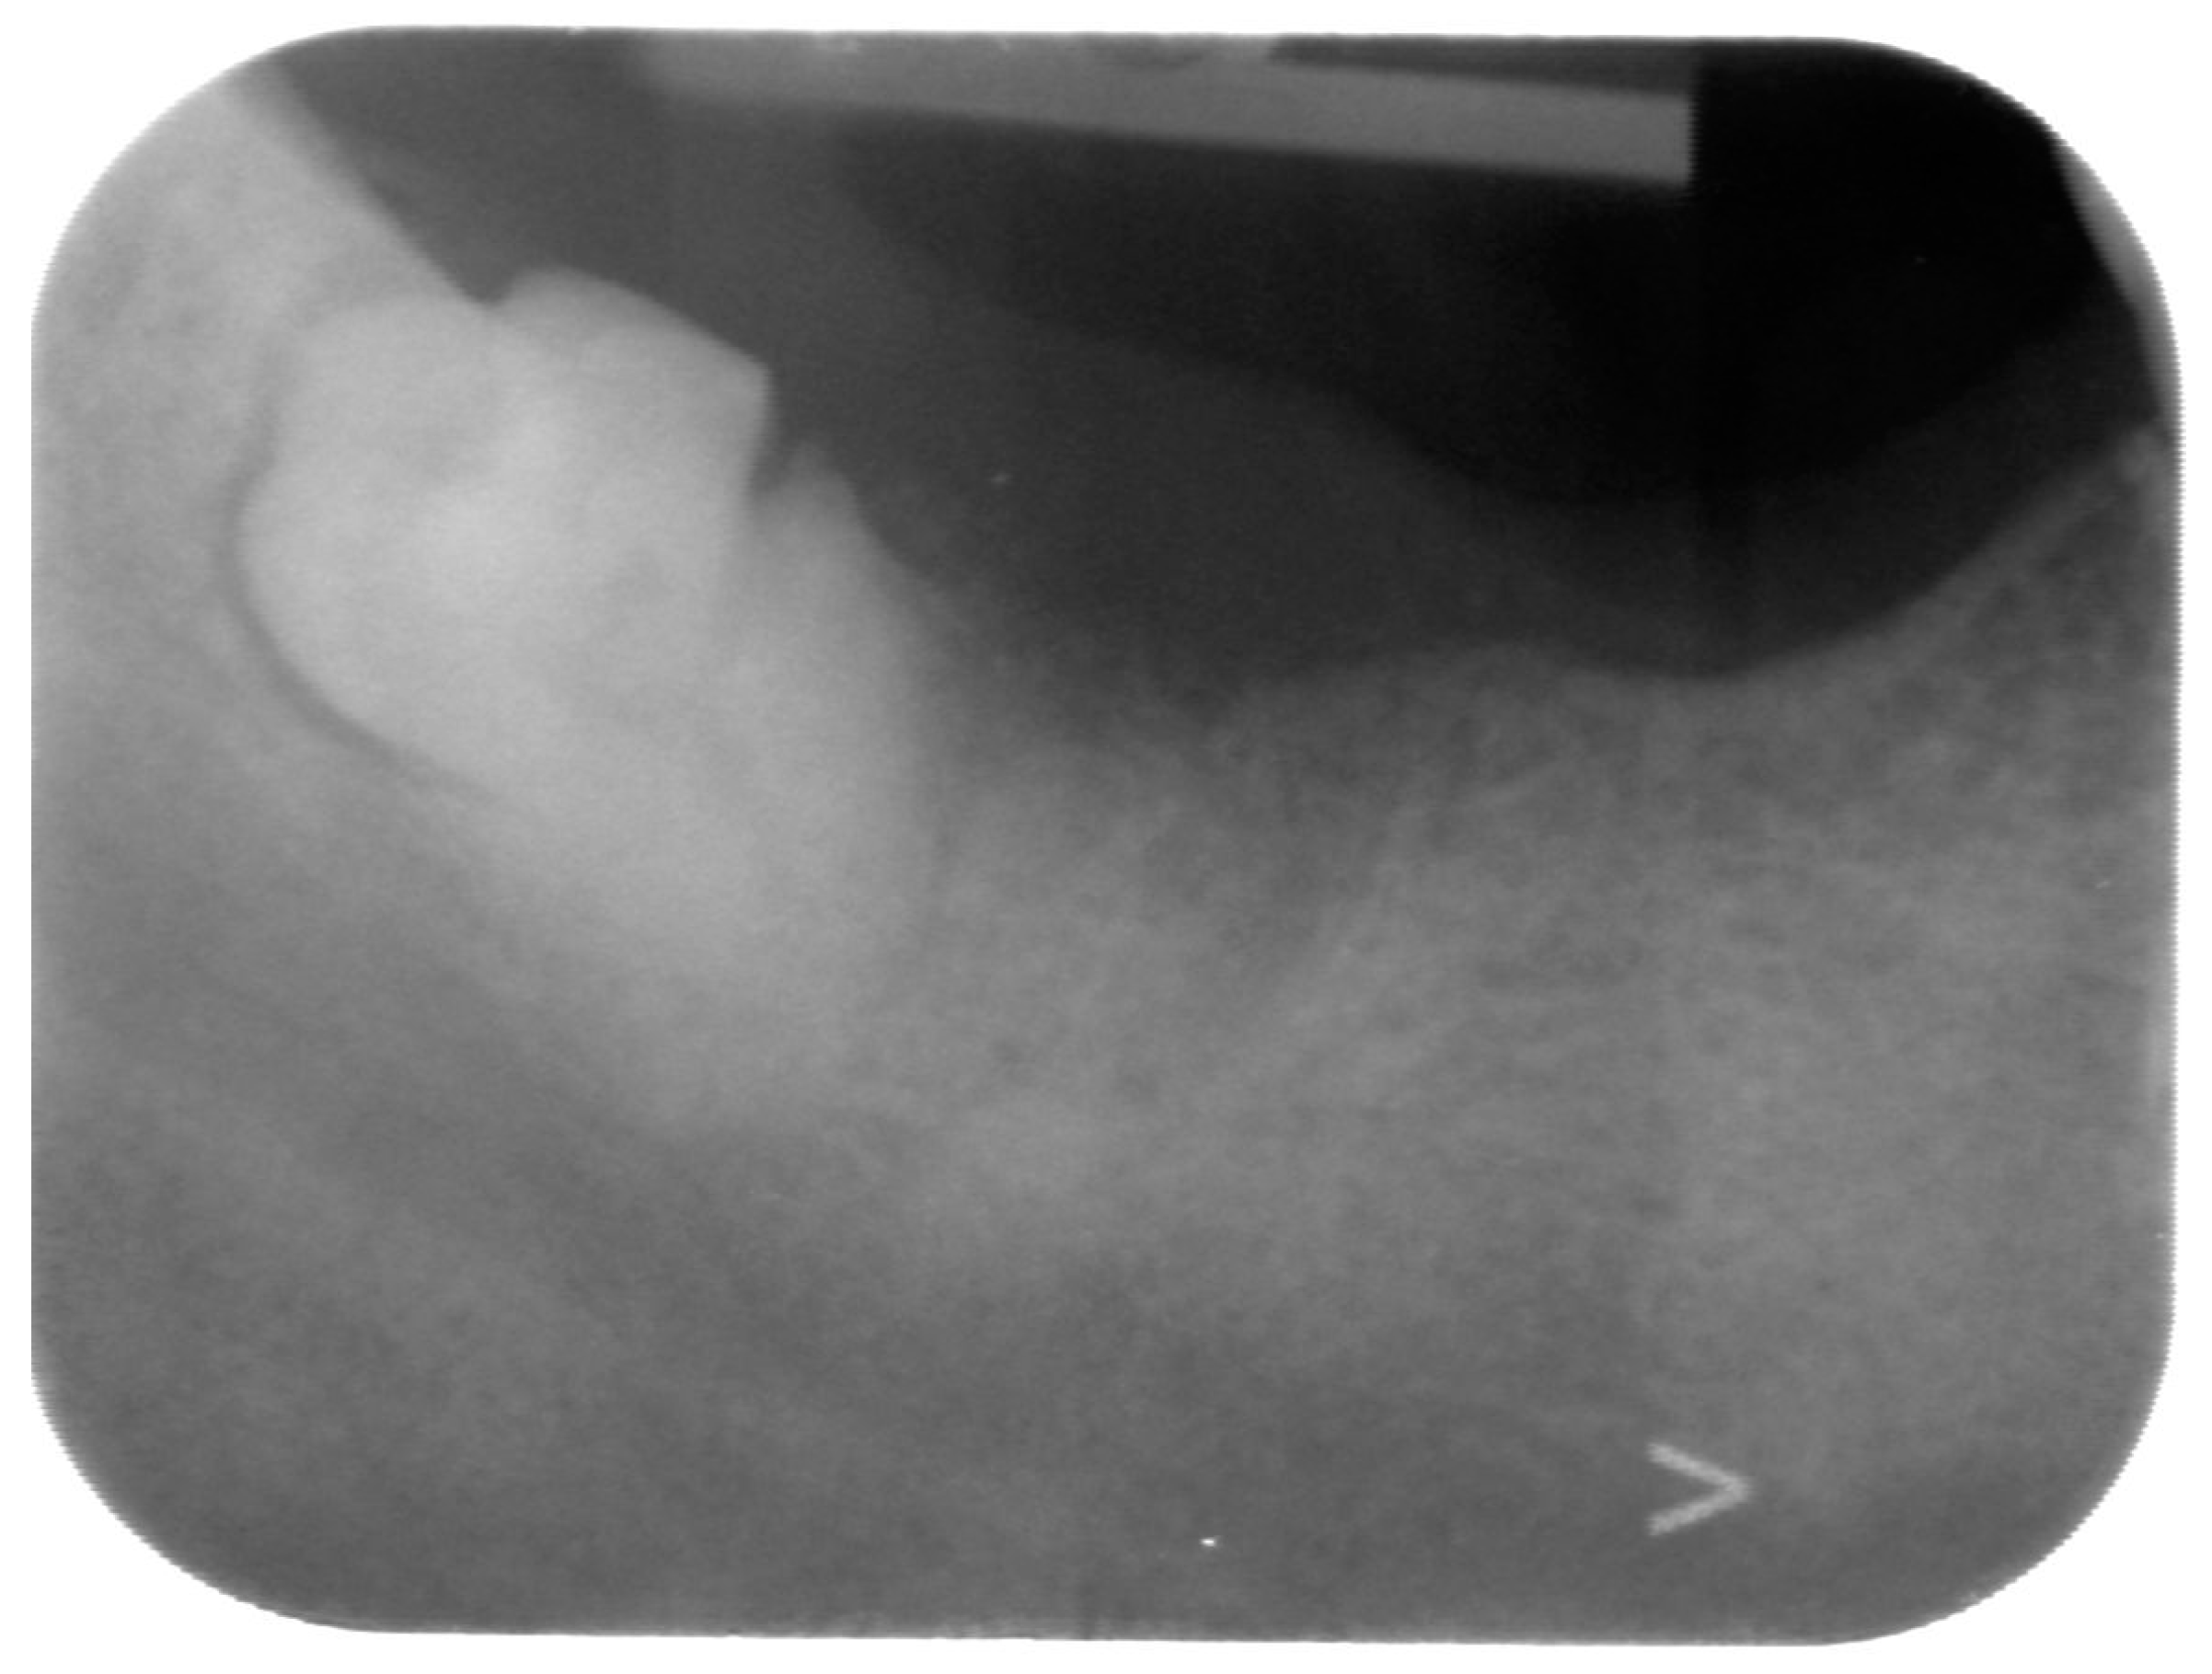

2. Detailed Case Description